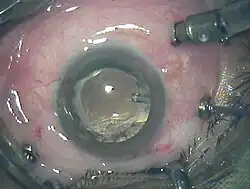

A vitrectomia é um procedimento cirúrgico pelo qual o vítreo é removida em um olho e substituído, geralmente com um gás ou líquido. Este procedimento é usado para o tratamento de diversas doenças oftalmológicas, como descolamento de retina, tromboses venosas, hemorragia e opacidades vítreas e buraco macular.[1][2]

A cirurgia de vitrectomia é precedida de exames oftalmológicas e seguida por uma sequência de procedimentos pré-operatórios. A internação se dá, normalmente, no dia da operação e exceto em casos especiais, o paciente não deve se alimentar e nem tomar água no mesmo dia. Na maioria das vezes, a cirurgia é realizada com a aplicação de anestesia local, sempre em ambientes adequadamente compostos por equipamentos sofisticados.[2]

A operação é feita através de três ou quatro micro incisões que permitem a utilização de instrumentos microcirúrgicos (fontes de iluminação, vitreófago, pinças, tesouras, endolaser, pontas de laser e sondas.) com diâmetros que variam de 0,9 milímetros (20 Gauge) a 0,5 milímetros (25 Gauge).[3]